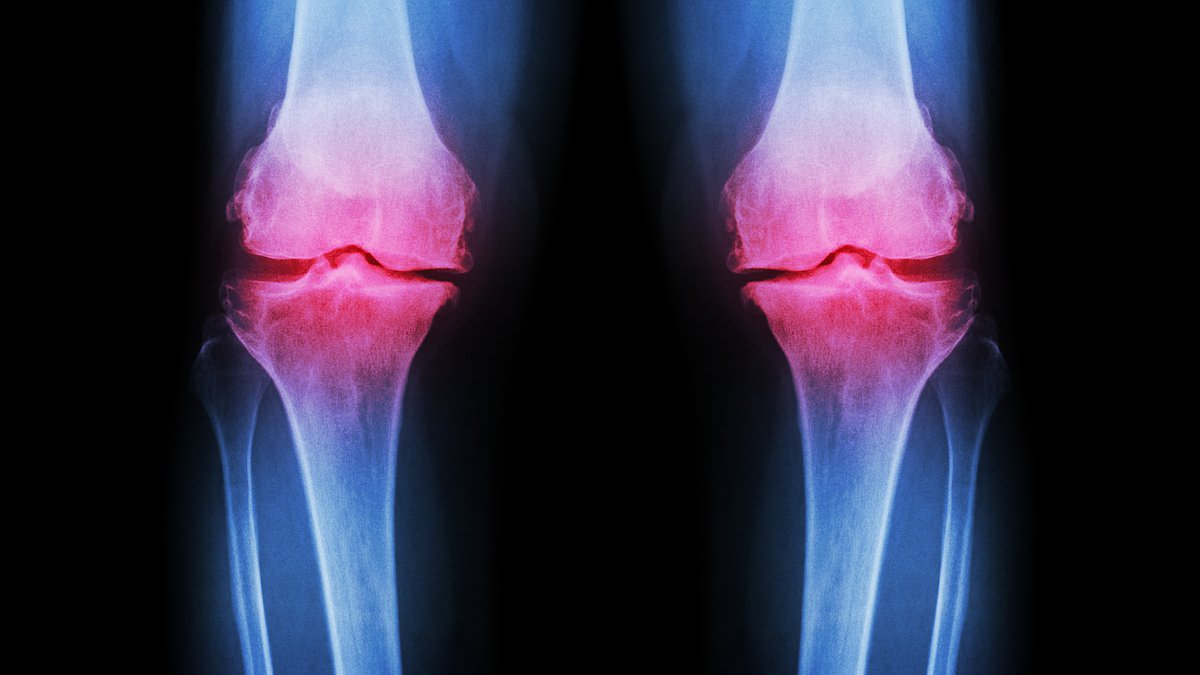

Osteoarthritis occurs when protective cartilage on joints wears down, leading to pain, stiffness, and reduced mobility. While joint damage is a normal part of life, the body typically repairs it. However, excessive stress from high-impact exercise and poor nutrition can overwhelm this natural process. Factors such as genetics, obesity, repeated stress on joints, and injuries all contribute to cartilage degradation. Post-traumatic osteoarthritis, for example, can result from fractures that affect joints, altering their mechanics and accelerating cartilage breakdown.